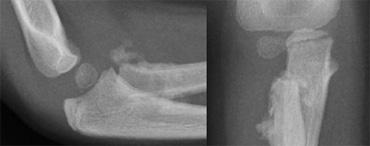

Supracondylar fractures. In A the anterior humeral line passes through the anterior third of the capitellum and in B even more anteriorly. Notice positive posterior fat pad sign in both cases

Gãy xương trên lồi cầu (2)

Nếu chỉ có di lệch tối thiểu hoặc không có di lệch, các gãy xương này có thể ẩn trên phim X-quang.

Dấu hiệu duy nhất sẽ là dấu hiệu đệm mỡ dương tính.

Thường có một số di lệch và đường cánh tay trước sẽ không đi qua trung tâm của chỏm con mà đi qua một phần ba trước hoặc thậm chí phía trước chỏm con (hình).